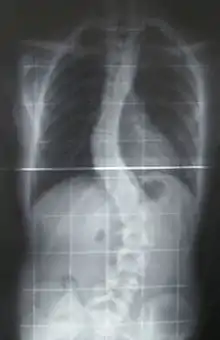

Preoperative (left) and postoperative (right) X-ray of a person with thoracic dextroscoliosis and lumbar levoscoliosis: The X-ray is usually projected anteroposterior, such that the right side of the subject is on the right side of the image; i.e., the subject is viewed from the rear (see left image; the right image is seen from the front). This projection is typically used by spine surgeons, as it is how surgeons see their patients when they are on the operating table (in the prone position). This is the opposite of many Chest radiographs, where the image is posteroanterior, i.e. projected as if looking at the patient from the front. The surgery was a fusion with instrumentation.